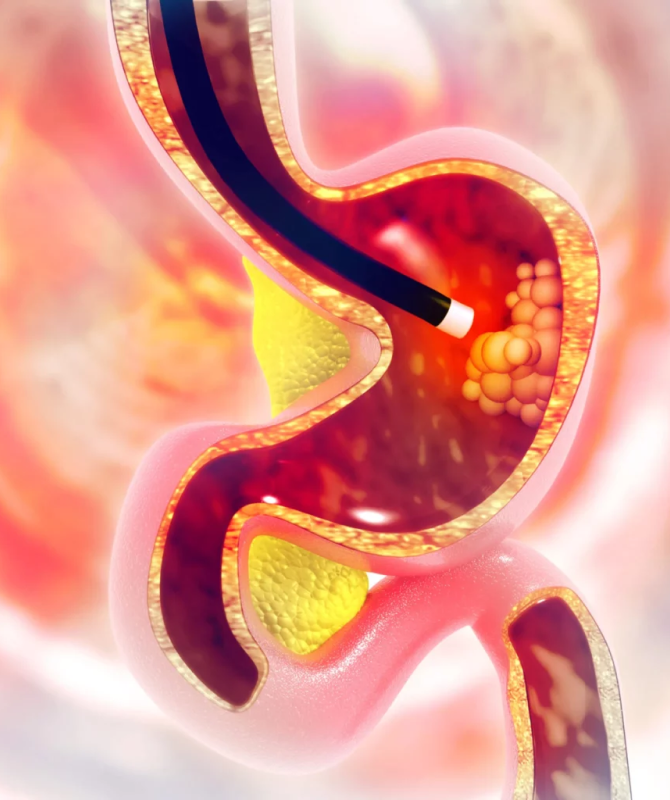

What is a gastroscopy?

Gastroscopy, also known as upper gastrointestinal endoscopy or oesophago-gastro-duodenoscopy (OGD), is a procedure where a tube with a light and camera on it is used to look for any physical changes on the surface of the upper digestive tract.